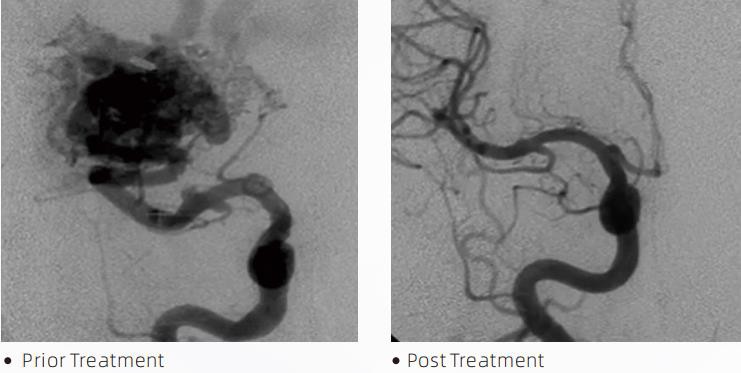

An LaibheTMIs teiripe endovascular idirghabhála é an Córas Embolic Leachtach chun anchuma cerebrovascular a chóireáil. Tagraíonn anchuma cerebrovascular do ghrúpa neamhghnáchaíochtaí néar-shoithíoch neamhurchóideacha nó urchóideacha a d’fhéadfadh a bheith mar thoradh ar hemorrhage intracranial, infarction cheirbreach, ischemia cheirbreach agus galair eile. Is feiste leighis é an córas embolization leacht a riartar trí chur isteach simplí infhéitheach, a embolizes soithigh fola cheirbreach neamhghnácha trí instealladh ábhar sreabhach speisialta. Cruthaíonn an t-ábhar sreabhach heambólacht fíocháin rialaithe laistigh de shoithí fola, rud a d'fhéadfadh tionchar anchuma cerebrovascular ar othair a laghdú. Úsáidtear micrea-chaititéar seachadta atá comhoiriúnach le DMSO a shonraítear lena úsáid sa néar-shoithíoch chun rochtain a fháil ar an suíomh heambólaithe. Is córas gníomhaire embolic leachtach neamhghreamaitheach é gníomhaire embolic leacht lava atá comhdhéanta de chomhpholaiméir EVOH (alcól vinil eitiléine) tuaslagtha i DMSO (sulfocsaíd démheitile), agus púdar tantalam micrónach ar fionraí chun codarsnacht a sholáthar don léirshamhlú faoi fhluarascópacht. laibheTMar fáil i dtrí fhoirmliú táirgí, LAVA-12, LAVA-18 agus LAVA-34. LAVA-12: Moltar nuair a bheathú micrea-soithí distal agus trí bheathaithe beaga. LAVA-18: Molta nuair a bheathú instealladh pedicle a dhéanamh in aice leis an nidus; LAVA-34: Arna mholadh le haghaidh sreafaí níos airde agus comhpháirteanna dornacha níos mó a leabú.